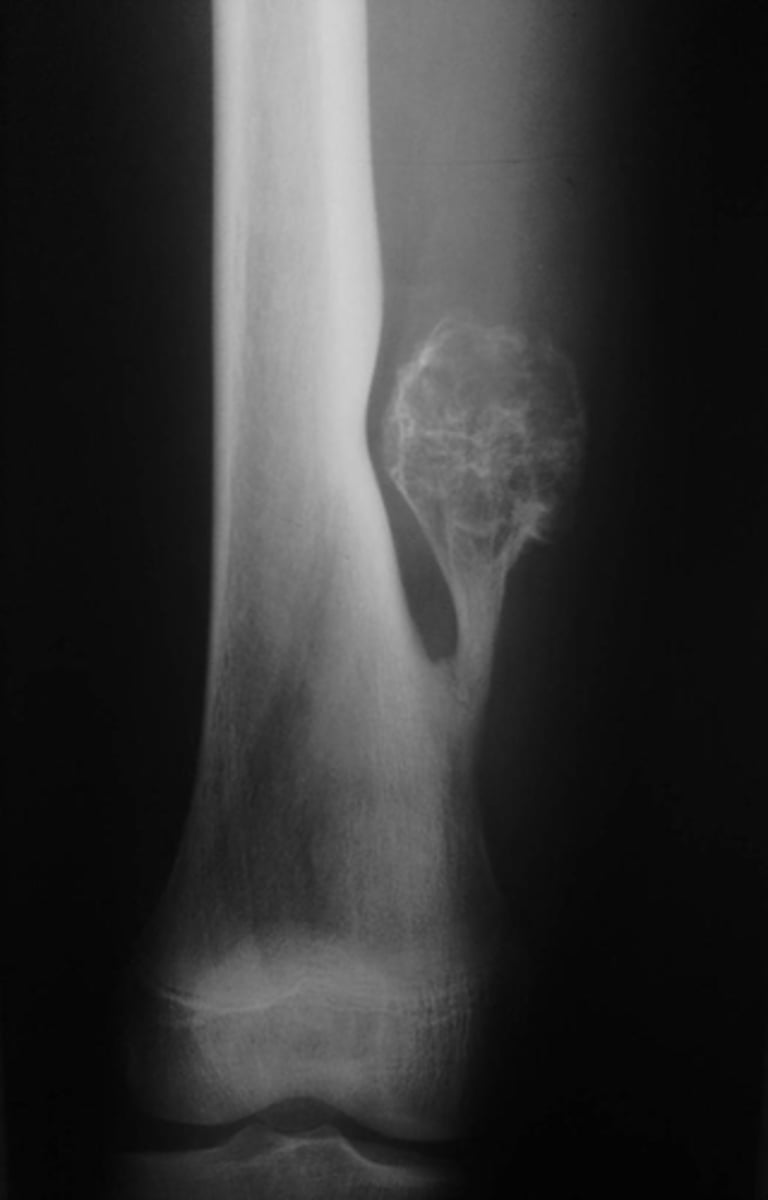

- Humerus

- Central

- Diaphysis

- Geographic

- Cortical thinning

Describe the lesion

<p>Describe the lesion</p>

Pathologic fracture

What complication has occurred?

<p>What complication has occurred?</p>

Simple bone cyst

Most likely diagnosis?

<p>Most likely diagnosis?</p>

Refer to orthopedist

Next step?

<p>Next step?</p>